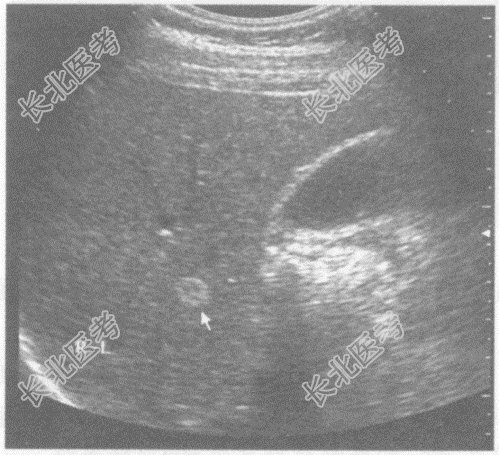

- 单项选择题临床资料:男性患者, 26岁,常规体检, HBsAg(-),AFP、CEA正常。

超声综合描述: 肝右叶可见1.4cm×1.0cm增强回声区,边界清晰, CDFI:内未见动静脉血流信号。

超声提示: A、肝转移癌

B、肝血管瘤

C、肝癌

D、肝腺瘤

E、肝脓肿